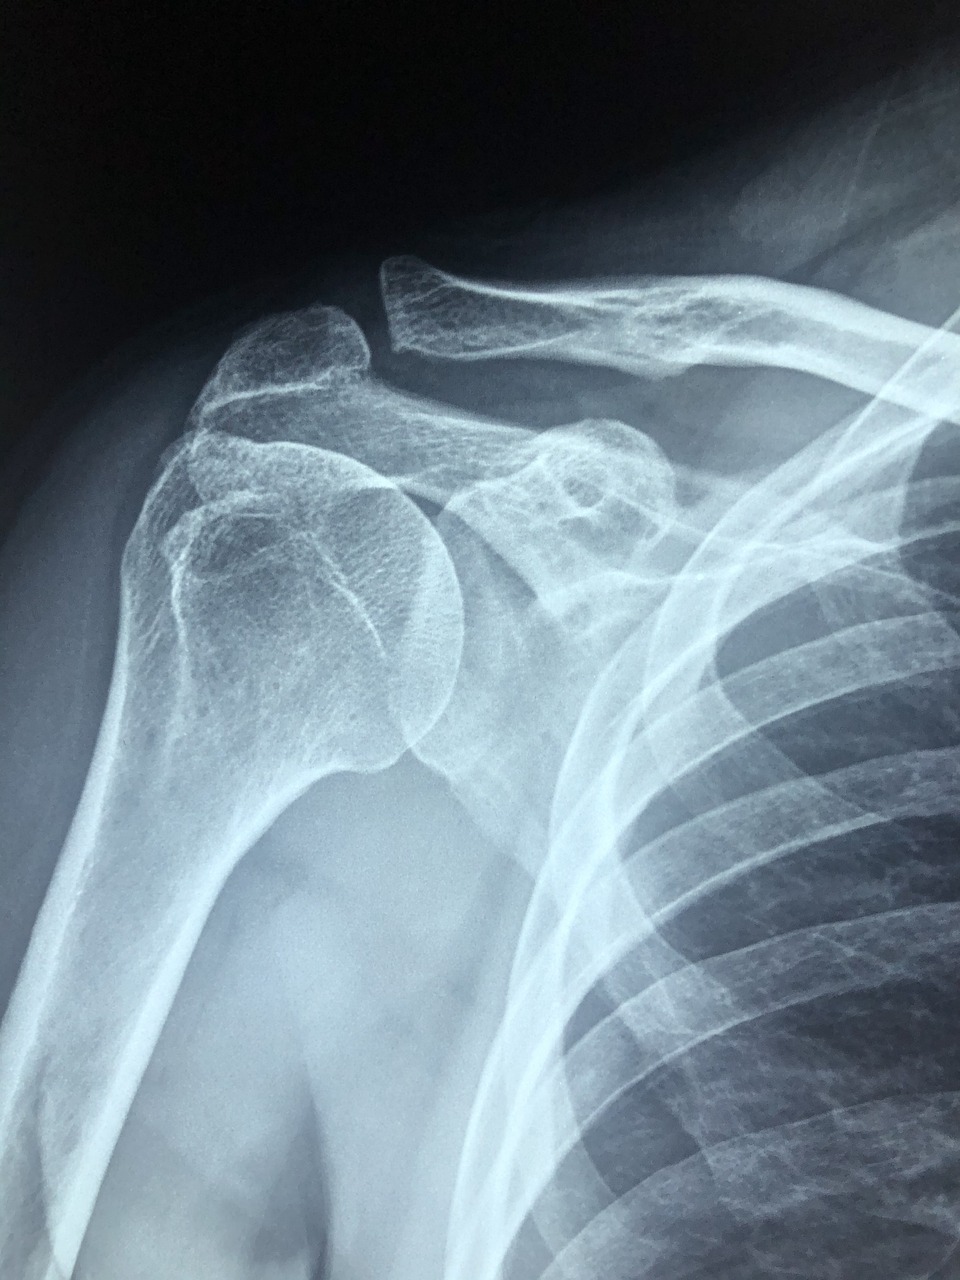

X-ray나 초음파 검사를 통해 석회 침착 여부를 확인하는 것이 중요합니다.

✅ 어깨석회화건염은 말 그대로 어깨 힘줄(회전근개)에 칼슘이 쌓이면서 생기는 염증 질환이에요.

시간이 지나면서 힘줄에 석회가 침착되며 염증과 통증을 일으키죠.